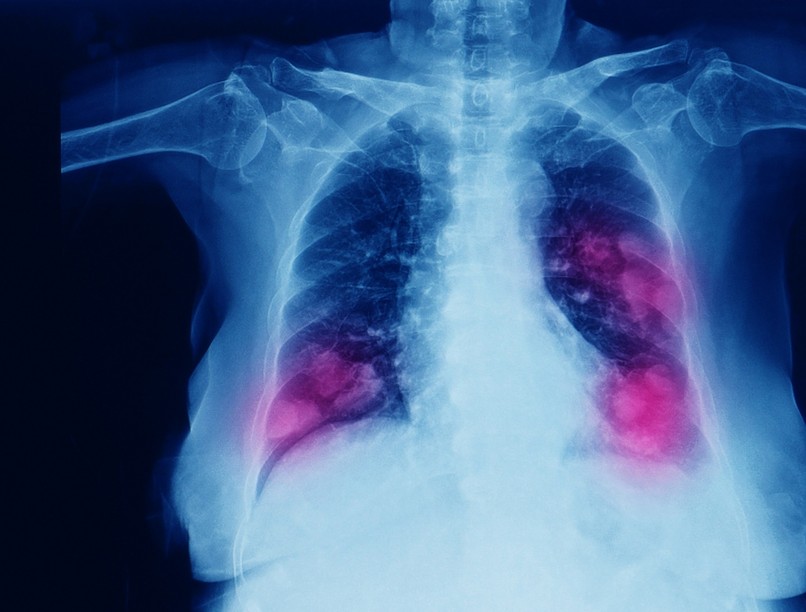

Tüdőrák: ez a kezelés növelheti a túlélési esély

A daganatos betegek közül a tüdőrákosok túlélési esélye az egyik legrosszabb. Ez a daganattípus „csendben” növekszik, kevés korai tünetet produkál, így diagnózisa az esetek több mint felében olyan késői stádiumban történik meg, amikor a műtét már nem jelent megoldást.